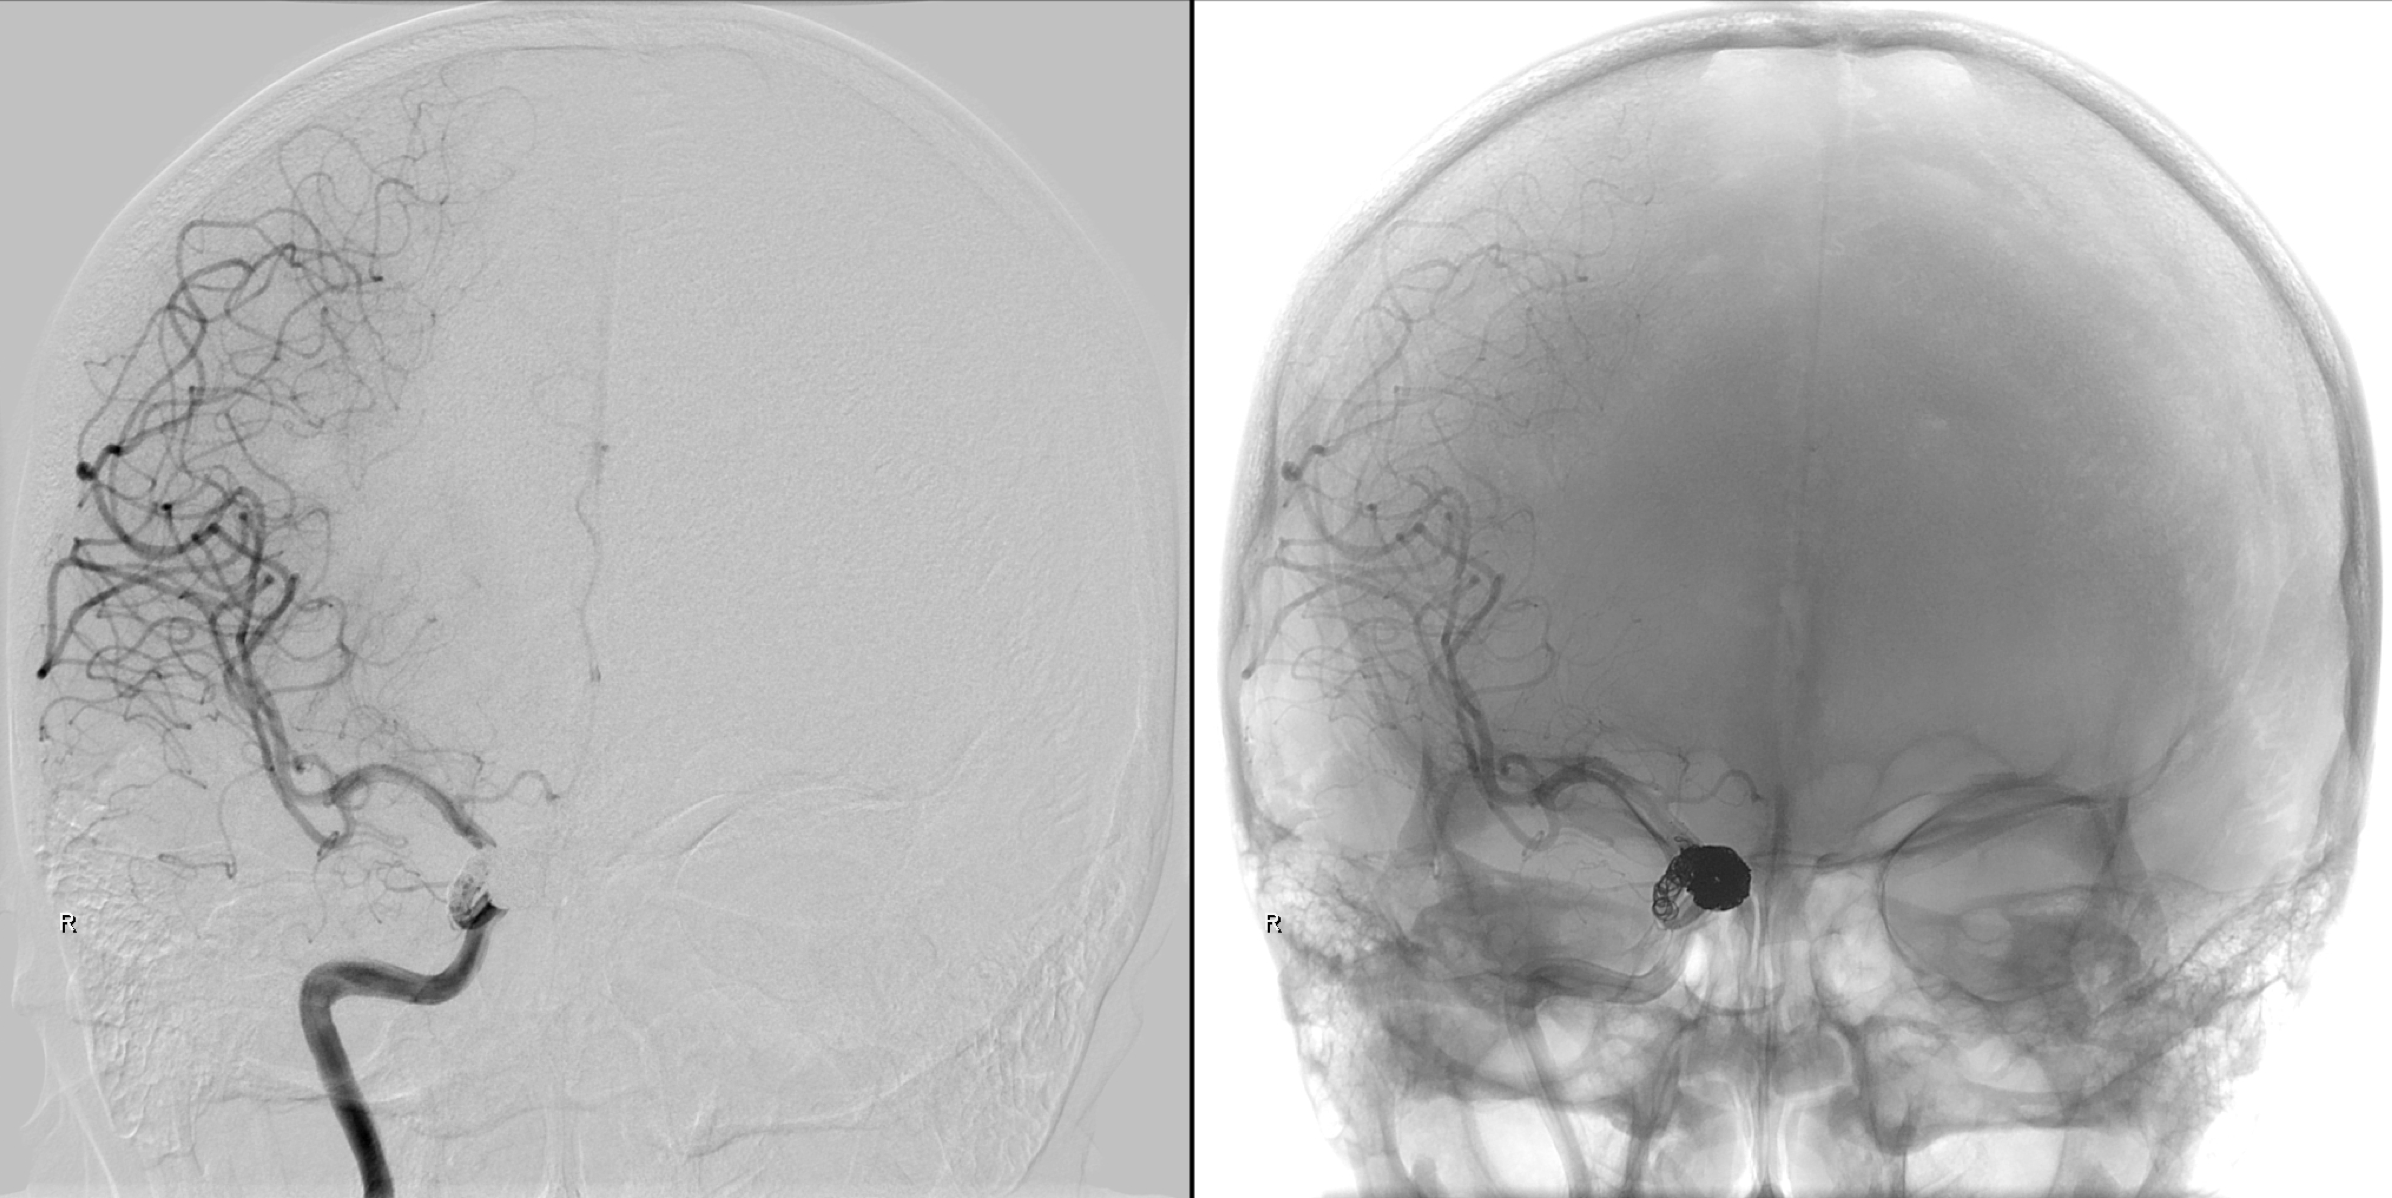

右侧颈内动脉正侧位造影:眼动脉段动脉瘤。

右侧颈内动脉三位造影重建:眼动脉段动脉瘤。给予支架辅助栓塞治疗。

不同工作位造影:动脉瘤完全栓塞,载瘤动脉通畅。

术后正位造影及蒙片显示:动脉瘤完全栓塞!

术后侧位造影及蒙片显示:动脉瘤完全栓塞!

蒙片显示:支架贴壁良好!部分弹簧圈被支架贴附于近端瘤颈及正常颈内动脉内壁!